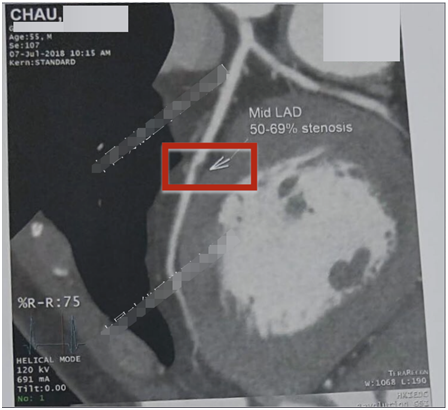

疾病史:胸闷、⽓短伴胸痛3年,尤其在活动后加重,在⾹港亚洲医学诊断中⼼诊断为,冠⼼病、⼼绞痛,2018年7⽉7⽇冠状动脉造影结果:左前降⽀(LAD)中段狭窄50-69%(⾮钙化斑块),医生建议放⽀架治疗。客户心有余悸,通过朋友介绍选择用功能医学方法治疗。功能医学干预4个⽉后,冠状动脉粥样硬化斑块消失,伴随的胸闷、胸痛也随之消失。

2018年7⽉7⽇,冠状动脉造影:左前降⽀(LAD)中段狭窄50-69%(⾮钙化斑块)